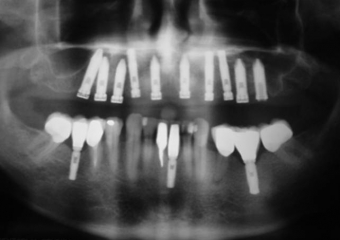

Raio X dos implantes